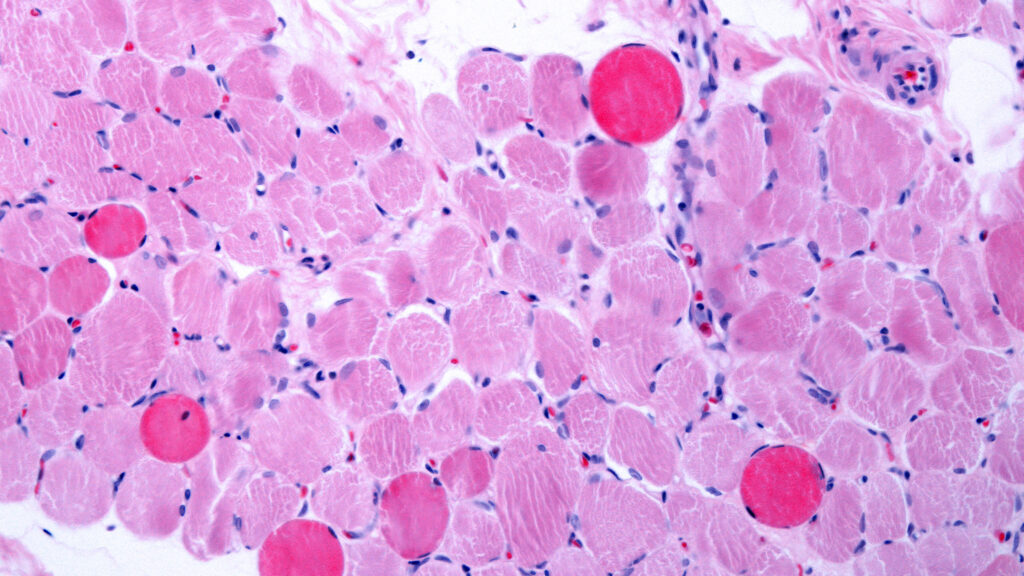

Duchenne muscular dystrophy is a severe genetic disorder characterized by progressive muscle degeneration and weakness. Patients with this condition often experience significant challenges in mobility and overall health. The potential approval of deramiocel could provide a much-needed treatment option for those affected by this debilitating disease.